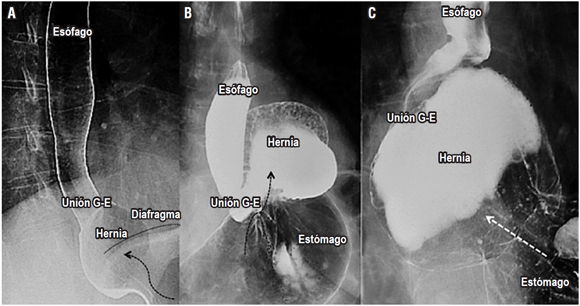

Hernia hiatal

La hernia hiatal es una protrusión del estómago a través del hiato esofágico al tórax que afecta del 10% al 50% de la población, y su diagnóstico y tratamiento tempranos previenen enfermedades de mayor complejidad 11,12. En la evaluación final del esofagograma, se debe identificar la presencia de hernias hiatales, definidas como un tamaño mayor de 2 cm entre la unión esofagogástrica y el hiato diafragmático (si es menor de 2 cm, la herniación es fisiológica) 11,12. El 95% de las hernias primarias son de tipo I (deslizadas) y los tipos II, III y IV se agrupan en las hernias paraesofágicas (más del 90% son de tipo III, y las menos comunes corresponden al tipo II). El reparo laparoscópico es el estándar de tratamiento, y el esofagograma es de utilidad para establecer el tamaño de la hernia, puesto que se requiere una amplia disección esofágica, el cierre adecuado del hiato (posible uso de malla) y un mecanismo antirreflujo 11,12 (Figura 4).